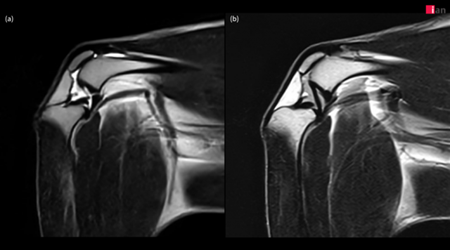

이안동물의학센터가 국내 동물병원 중 최초로 도입한 AI 기반 MRI 소프트웨어를 통해 무릎(Stifle joint) MRI 촬영 화질을 획기적으로 향상시키며 반려동물 정형외과 진단의 새로운 기준을 제시하고 있다고 31d일 밝혔다.

특히 이안동물의학센터는 이 소프트웨어로 복잡한 무릎 관절 내 구조물에 대한 세밀한 관찰이 가능해지면서 정확한 진단과 치료 전략 수립에 있어 큰 진전을 이루고 있다.

2023년 말부터 본격 가동된 이안동물의학센터의 AI 기반 MRI 소프트웨어는 딥러닝 알고리즘을 활용해 노이즈를 효과적으로 제거하고, 이미지 선명도를 대폭 향상시켰다.

특히 무릎 관절처럼 작은 구조물들이 복잡하게 얽혀 있는 부위에서 기존 영상 기법으로는 명확하게 파악하기 어려웠던 인대, 연골, 활액낭 및 인접한 근육 등의 세부 구조물까지 뚜렷하게 확인할 수 있어 정밀 진단에 큰 도움이 되고 있다.

이안동물의학센터는 정형외과에서 무릎 질환은 MRI로 진단하기에 가장 까다로운 분야 중 하나라며, AI 기술을 통해 MRI의 화질이 개선됨에 따라 십자 인대 파열, 연골 손상, 활액막 질환, 힘줄 질환 등 다양한 무릎 질환을 보다 빠르고 정확하게 진단할 수 있게 됐다고 설명했다.